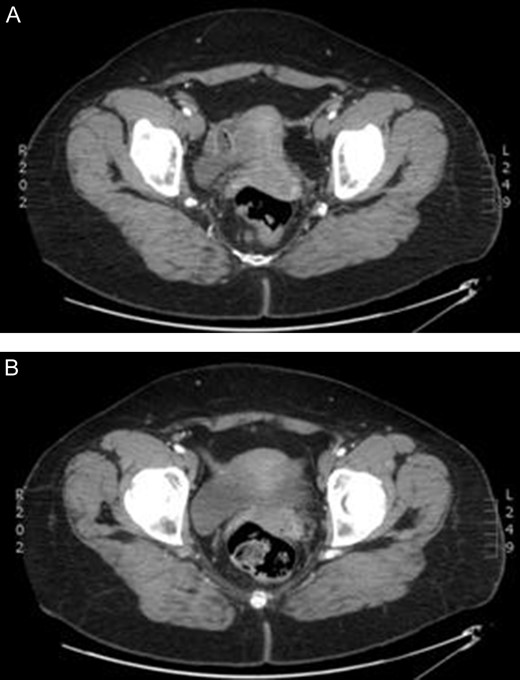

In anticipation of arterial occlusive disease, an urgent CT angiogram of the aorta and lower extremities was performed with unexpected results. Bilateral sciatic arteries supplying the popliteal arteries were identified (Figs 2A and 3A). Native bilateral superficial femoral arteries were present but small in comparison. The right sciatic artery was occluded at the sciatic notch (Figs 2B and 3B) with reconstitution of the artery within the mid thigh. Distal to this, the posterior tibial and peroneal arteries were patent. The proximal anterior tibial artery was patent, but distally occluded. There was no stenosis or occlusion on the left, with three-vessel run off below the knee.

Enhanced computed tomography scan of a 52 year old woman with right lower limb ischaemia showing (A) bilateral persistent sciatic arteries entering greater sciatic foramen, and (B) a few slices inferiorly a thrombus occluding the right sciatic artery.